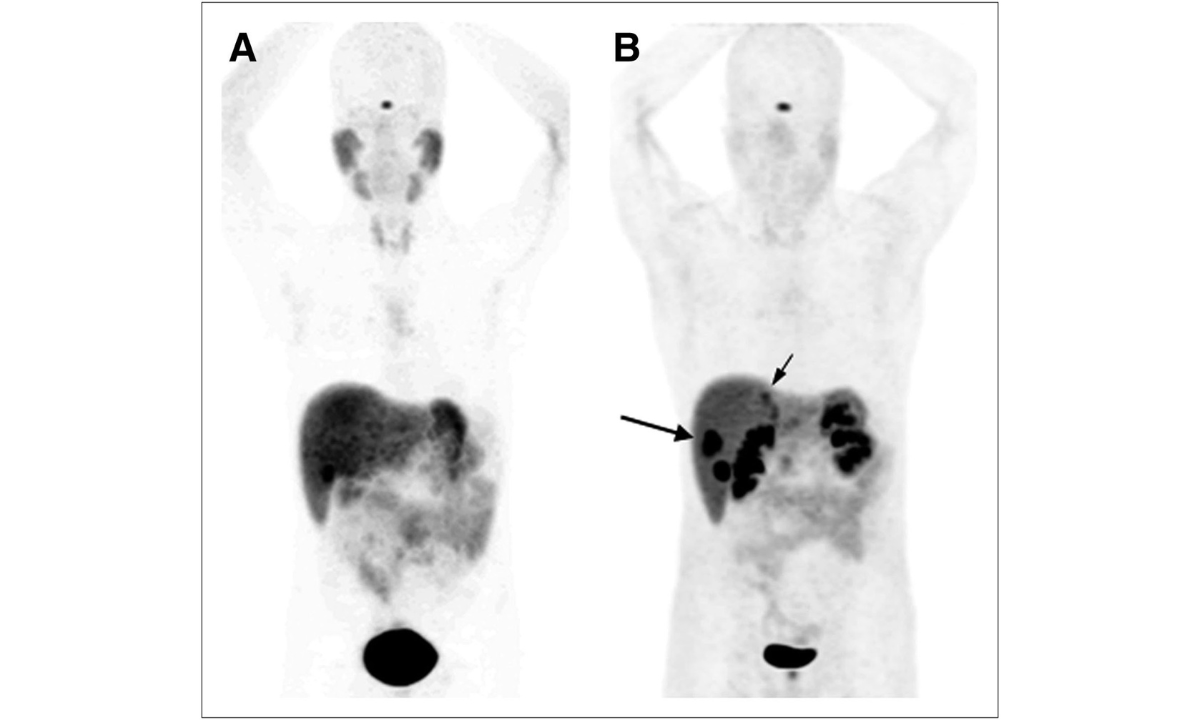

- DOTA PET scan identifies tumors by targeting somatostatin receptors

- DOTANOC PET scan in Bangalore is particularly valuable for staging and detecting small metastases

These scans allow us to see disease activity at a molecular level, which conventional CT or MRI may miss.